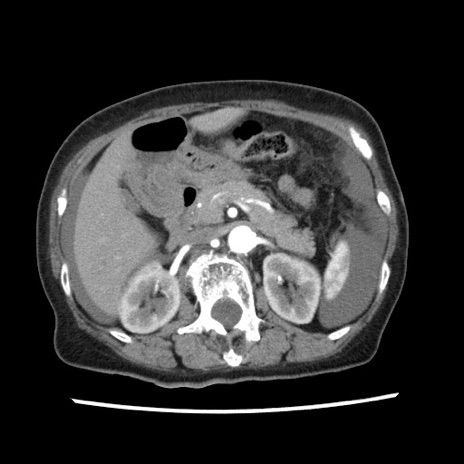

症例1(横断像)

【症例】80歳代女性

【主訴】腹痛

【現病歴】8時間前から腹痛あり来院。

【既往歴】糖尿病、脂質異常症、子宮体癌にて子宮全摘術

【身体所見】意識清明・会話良好だが腹痛で苦悶様、全腹部にわたって反跳痛と圧痛あり

【データ】WBC 13600、CRP 0.14、LDH 224、CK 90